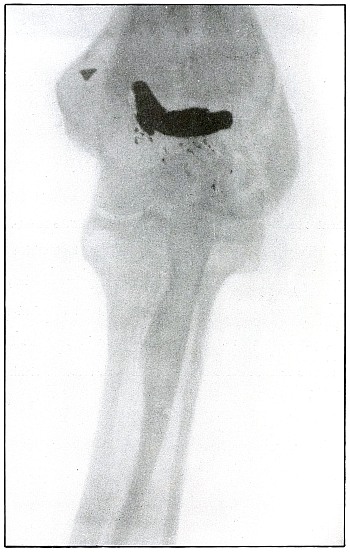

Plate 52.

[Pg 115]

Rifle—Plate 52.

LOWER EXTREMITY.

Gunshot Fracture of the Upper Shaft of the Femur.

The course of the bullet was anteroposterior and pierced the axis

of the shaft of the femur with three radiating lines of fracture,

resulting from the perforating action of the bullet striking the bone

at long range and with greatly reduced energy.

This plate shows the lateral separation of large fragments,

which is typical of gunshot wounds of long range.

Such wounds are usually not infected.

Emergency treatment is antiseptic dressing and coaptation with

extension and temporary splint, so that it may support the bone for

transportation and may be easily removable at place of continued

treatment.

In these cases with lateral separation of fragments, it is imperative

to supplement extension with pressure in a line perpendicular to the

long axis of the femur.

[Pg 116]